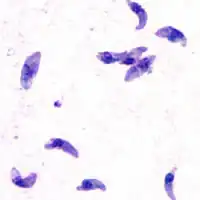

| Giemsa stained T. gondii tachyzoites, 1000× magnification | |

Tachyzoites

Motile, and quickly multiplying, tachyzoites are responsible for expanding the population of the parasite in the host.[29][30]: 19

When a host consumes a tissue cyst (containing bradyzoites) or an oocyst (containing sporozoites), the bradyzoites or sporozoites stage-convert into tachyzoites upon infecting the intestinal epithelium of the host.[30]: 359 During the initial acute period of infection, tachyzoites spread throughout the body via the blood stream.[30]: 39–40